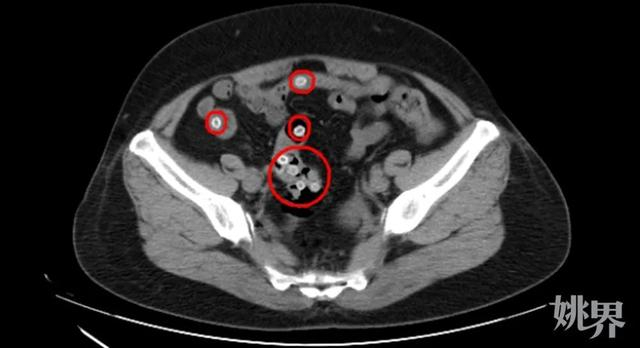

CT影像显示,王阿姨的肠内存在多处类圆形高密度影,密密麻麻的圆圆小白点正是滞留在肠道内的杨梅核,这是导致患者腹痛不止的罪魁祸首。

CT影像显示,患者肠道内有不少杨梅核滞留

“这种情况下,患者很有可能会引发胃痉挛和肠梗阻,要尽快将杨梅核排出体外。”医生首先为患者进行解痉止痛治疗,然后为其开具了通便的药物促杨梅核排出。